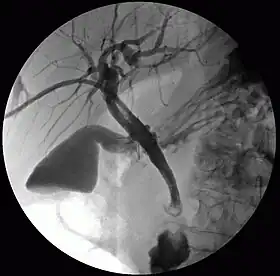

| Percutaneous transhepatic cholangiography | |

Percutaneous transhepatic cholangiography, percutaneous hepatic cholangiogram (PTHC) is a radiological technique used to visualize the anatomy of the biliary tract.[1] A contrast medium is injected into a bile duct in the liver, after which X-rays are taken. It allows access to the biliary tree in cases where endoscopic retrograde cholangiopancreatography has been unsuccessful. Initially reported in 1937, the procedure became popular in 1952.[2][3]